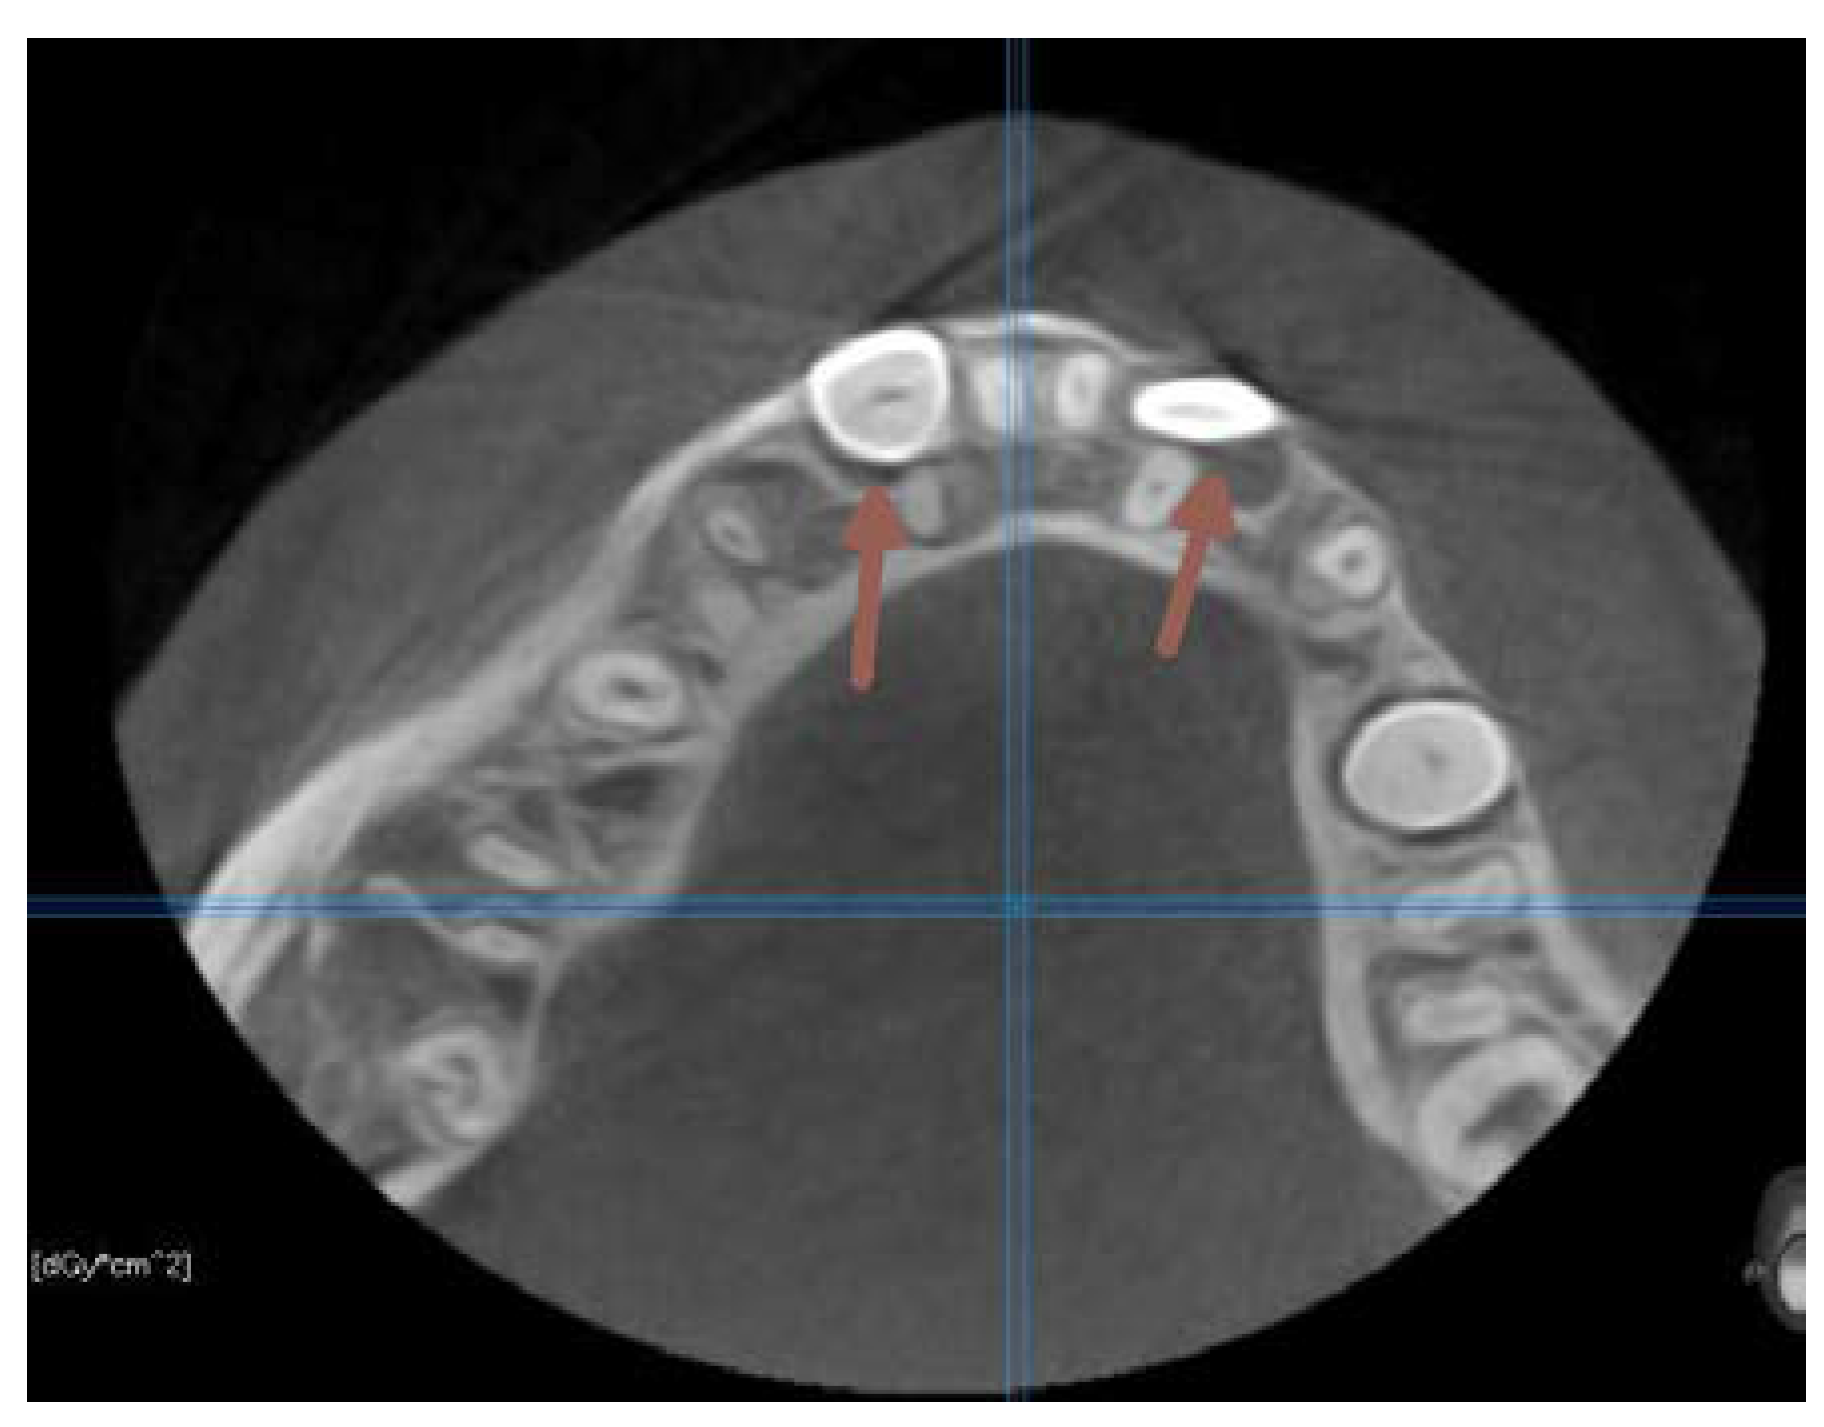

The next two OPG x-rays were taken after 11 months. On the latter (2017) (Figure 5) it became clear, that 22 and 11 were inhibited in eruption. ( DA 9,1 and 9,3, CA 12 y 11 mths) The patient was referred to the second CBCT scan image reproduction to make clear the underlying surgical situation. (Figure8). The CBCT scan revealed the position of supernumerary teeth also in the lower dental arch. (Figure 8.,9.)

Figure 9. The CBCT taken in 2017. Axial section on the level of premolars .

At this time the 33 and 43 were slowing down their eruption, therefore another surgical intervention was needed. Another CBCT scan image was necessary to prove the proximity of the crowns of the lower canines to the apical area of the lower lateral incisors. (Figure 15).